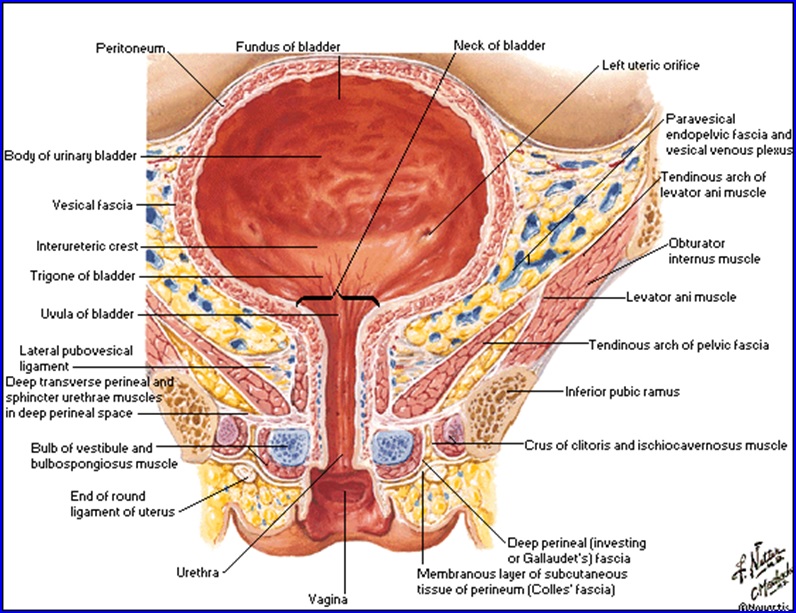

Vezica urinară la femeie: